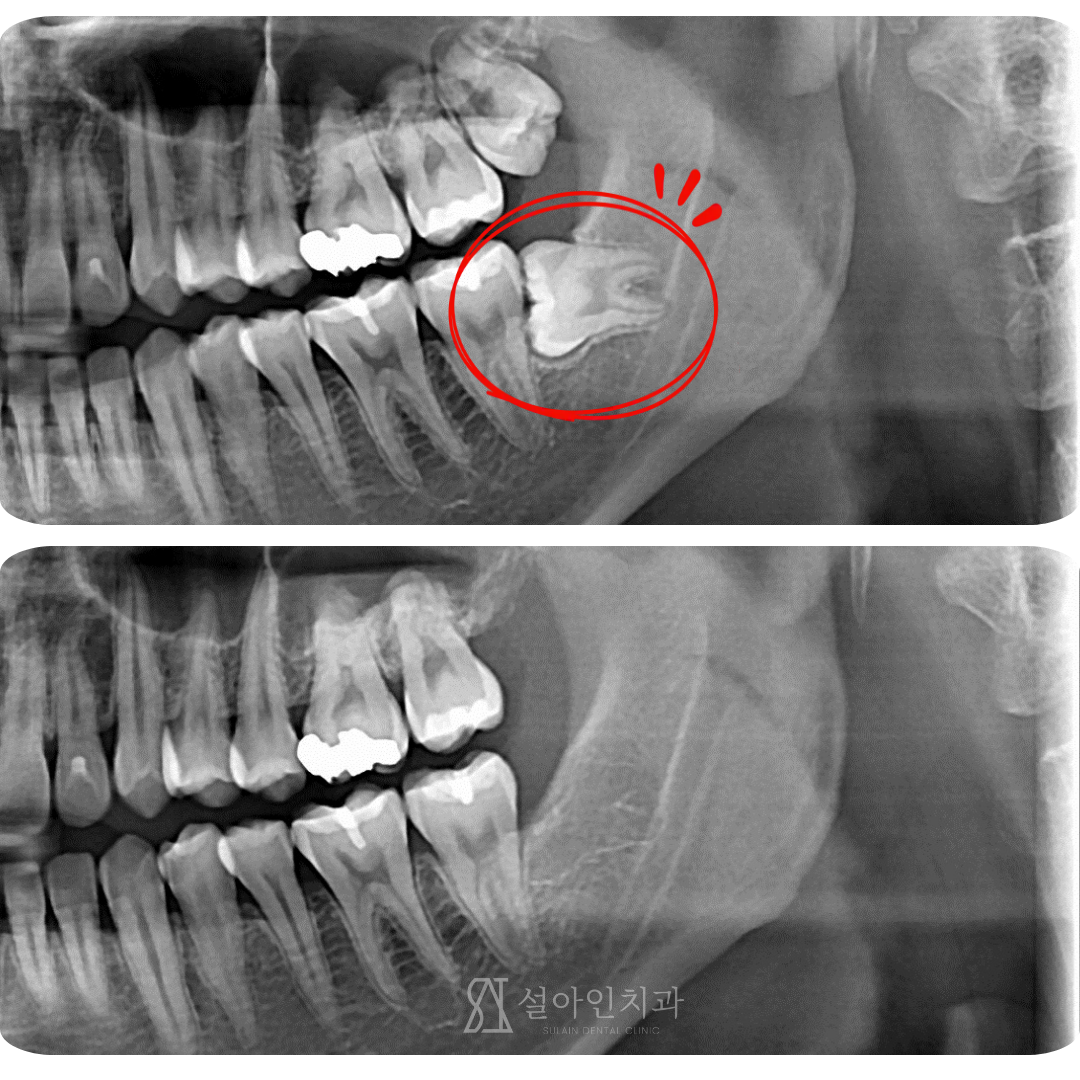

욱신거리는 사랑니, 잇몸은 왜 붓고 피가 날까요? (사랑니 부었을 때 대처법)